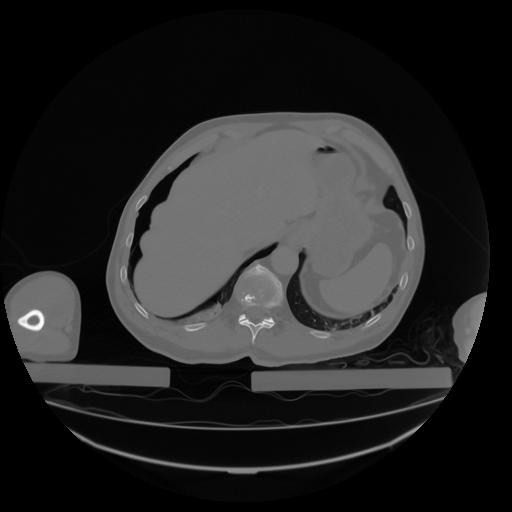

27 CUERPO,CE,Axial,3.0,CUERPO,,